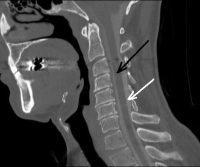

(Click to Enlarge Image) Post operative XP x-ray of the laminoplasty. Please note that the spinous processes (noted by the white lines) are “off center” in the area of surgery as the back wall of the canal that the spinous processes attach is rotated to the side to open the canal.